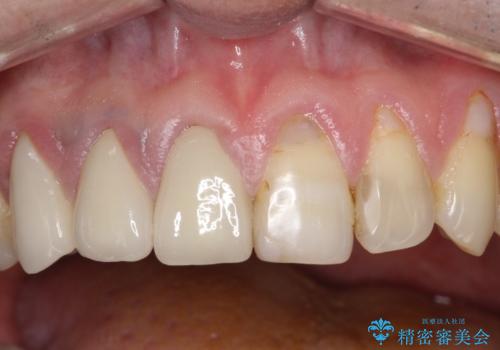

不自然な前歯のかぶせ物をオールセラミックへ

金属の土台を、ファイバーコアという歯根にやさしく白いものに交換して、かぶせ物をオールセラミックにしました。